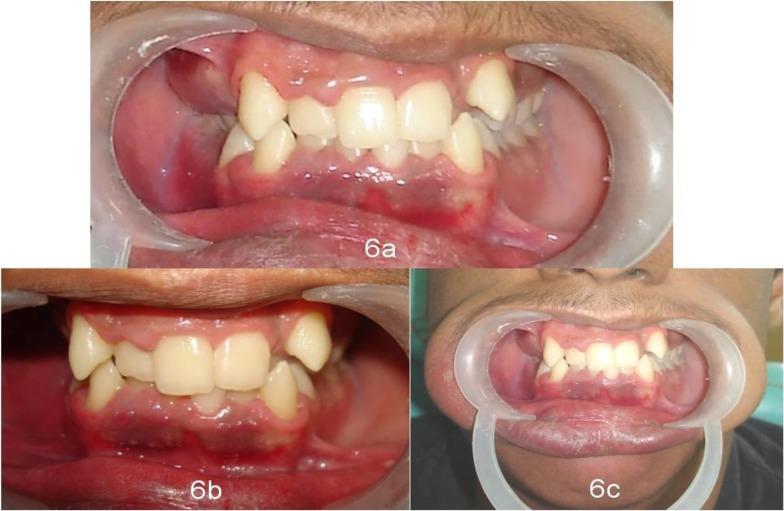

Sturge-Weber syndrome (SWS) is a rare congenital neurocutaneous disorder. It is characterized by the presence of facial port wine stains, neurological abnormalities like seizures and mental retardation, ocular disorders, oral involvement and leptomeningeal angiomas.

A 13-year-old boy presented with the chief complaint of swollen, bleeding gums and deposits on the teeth. Detailed medical and dental history, clinical examination and investigations confirmed the diagnosis of Sturge-Weber syndrome. The treatment comprised of a thorough plaque control regimen to reduce the gingival enlargement, and it included oral hygiene instructions, thorough scaling, root planing at regular intervals and plaque index scoring which motivated the patient at each visit.

This case illustrates that early intervention in a patient with Sturge-Weber syndrome is quintessential because of its associated gingival vascular features and their complicating manifestations. Furthermore, the need for periodic oral examinations and maintenance of good oral hygiene to prevent any complications from the oral vascular lesions has been highlighted.